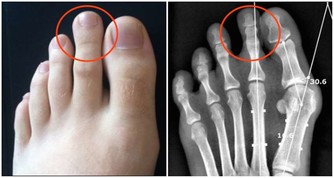

(7)皮膚發黑變粗:骨癌

這是骨癌的信號,不少胃癌患者在未發現任何症狀時,其腋下、肚臍周圍和大腿內側的皮膚會變黑變粗;有的患者面容和掌心皮膚也略呈黑色。